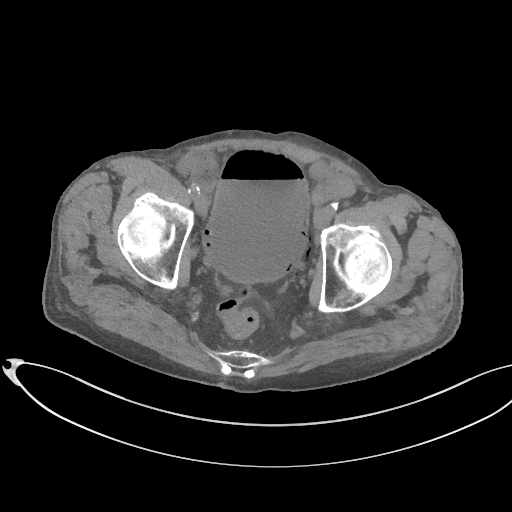

Figurile 1 şi 2: axial examinare CT abdomen şi pelvis fără substanță de contrast

Video 1: axial examinare CT abdomen şi pelvis fără substanță de contrast

Discuţie caz nr 131: pacient de 85 de ani cunoscut diabetic este adus la camera de gardă pentru dureri abdominale difuze, efectueaza CT fără substanță de contrast deoarece eGFR este 21 mL/min/1.73 m². Se evidențiază pericardita în cantitate medie, mai multe chiste renale – unul spontan hiperdens, multiple plăci aterotrombotice calcificate la nivelul aortei și ramurilor precum și multiple bule aerice în peretele vezicii urinare și conținut hidro-aeric al vezicii urinare. Ultimele două elemente sugerează diagnosticul de cistita emfizematoasă.